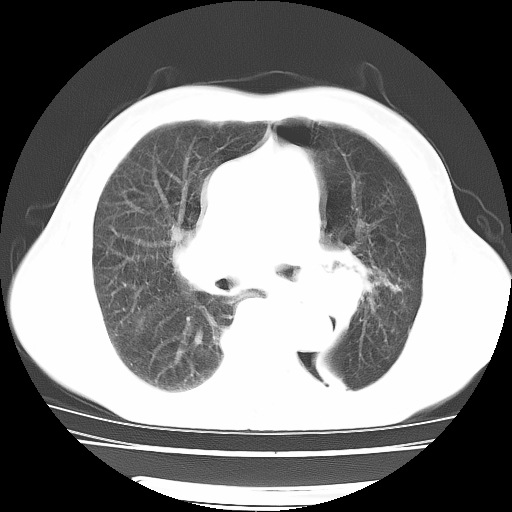

男,71岁,咳嗽,气喘10年,再发并咯血.胸片见气胸

考虑  左肺中心型肺癌伴阻塞性肺炎,肺不张,纵膈淋巴结肿大。慢支炎,肺气肿,左侧气胸肺压缩5%

左侧中央型肺癌伴纵膈淋巴结转移。

左肺中心型肺癌伴阻塞性肺炎,肺不张,纵膈淋巴结肿大

1)考虑左肺中心型肺癌伴阻塞性肺炎、左肺下叶肺不张、左侧肺气肿,纵膈淋巴结转移。2)左侧气胸(肺组织压缩约5%)。

左肺中心型肺癌伴阻塞性肺不张、肺气肿 。

1)考虑左肺中心型肺癌伴阻塞性肺炎、左肺下叶肺不张、左侧肺气肿,纵膈淋巴结转移。2)左侧气胸。